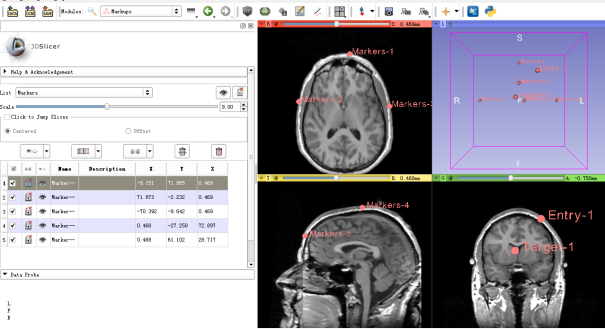

- 2 Define “Markers”, “Target Point” and “Entry Point” using the Markups module.

- 3 Load the defined fiducial lists

- 1 Select the fiducial list - Markers as the markers which define the reference planes.

- 2 Select the fiducial list – Target as the target point

- 3 Select the fiducial list – Entry as the entry point